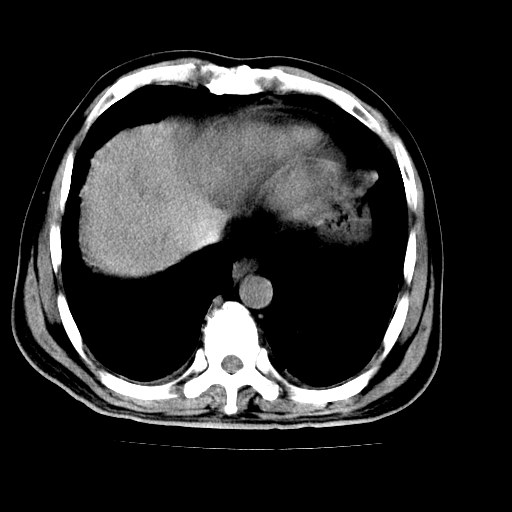

男,66岁,上腹部不适、黄染一周。彩超示:肝左叶占位,肝内胆管扩张,胆总管扩张,胆总管占位?

肝左叶不规则软组织肿块影,边缘不规整邻近肝实质受累分界不清;肝内胆管(左叶)明显扩张成“软藤状”,诊断:肝左叶胆管细胞癌。

肝左叶占位性病变,并胆管扩张,符合胆管细胞癌ct表现,门脉左支受累,左肾囊肿。窗宽太窄了,其他的看不清

左叶胆管细胞癌累及胆总管,门脉左支受侵,慢性胆囊炎胆结石,左肾小囊肿